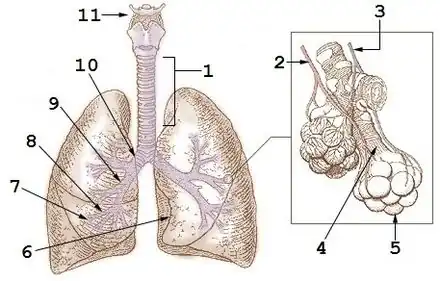

Poumon

2 : Veine pulmonaire

3 : Artère pulmonaire

4 : Conduit alvéolaire

5 : Alvéole pulmonaire

6 : Incisure cardiaque

7 : Bronchioles

8 : Bronche tertiaire (segmentaire)

9 : Bronche secondaire (lobaire)

10 : Bronche primaire (souche)

11 : Larynx